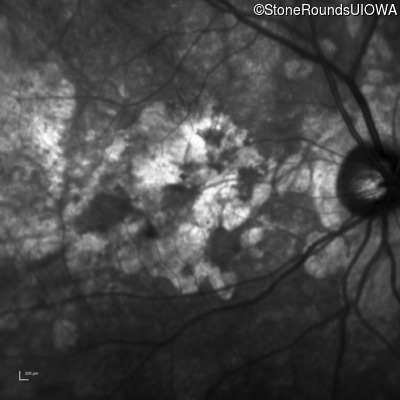

Age at visit: 64 years

This 64 year old woman first noticed some distortion in her vision at age 46 while looking at graph paper.

Age at visit: 65 years